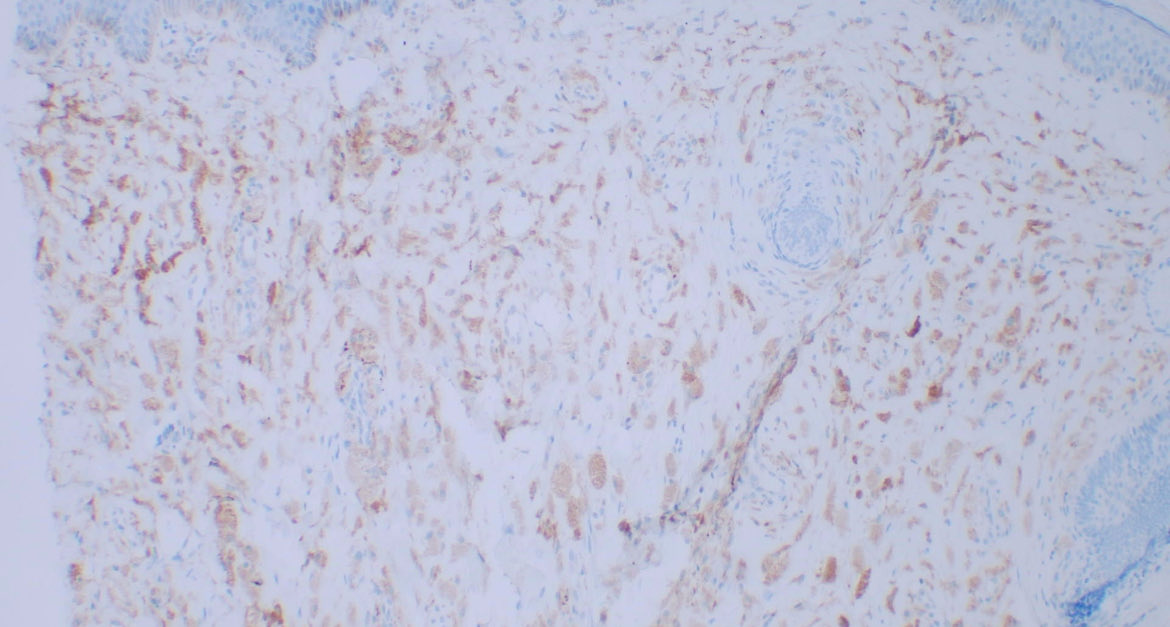

Non-neural granular cell tumor Intradermal tumor with cells showing granular cytoplasm. S100 and Sox10: negative HE, CD68, CD56 #path #pathology #dermtwitter #dermatology